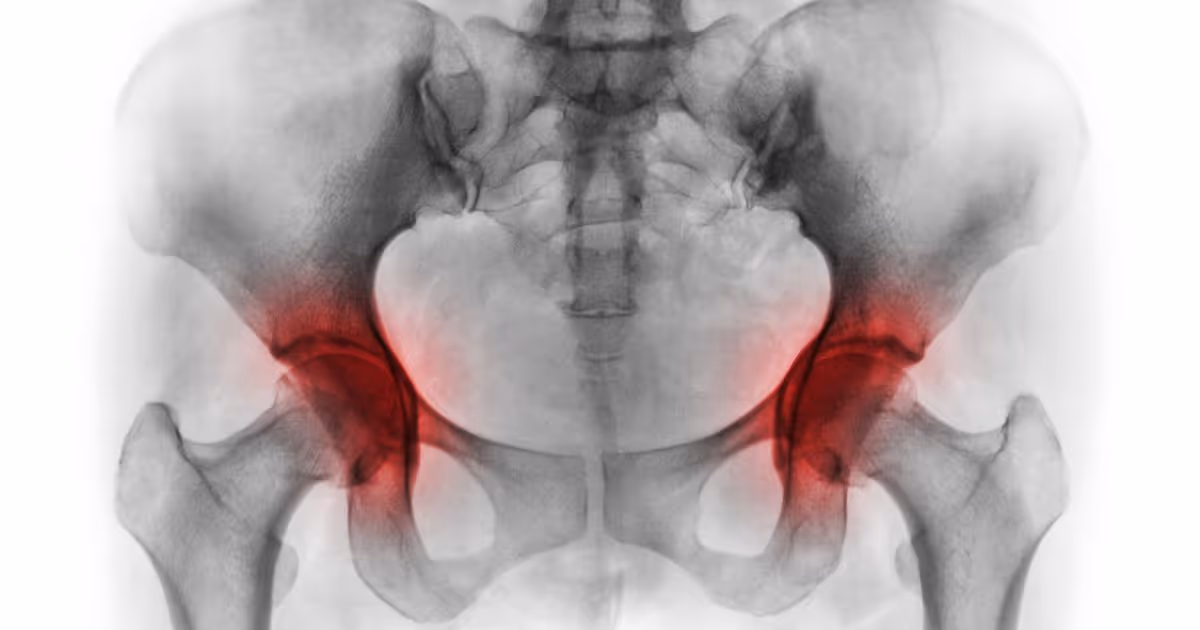

Hip replacement (hip arthroplasty) is a surgical procedure to treat severe hip degeneration involving removing degenerative hip joints and replacing them with a new artificial hip joint to treat severe hip pain, hip stiffness, or groin pain due to hip osteoarthritis, osteonecrosis of the femoral head, or femoral neck fracture. Hip replacement helps relieve hip pain, improves mobility for activities including getting up, sitting, standing, and walking, decreases dependency, and enables patients to resume their normal daily activities.

• Hip X-rays examine the entire hip joint structure, including the femoral head, acetabulum, and articular cartilage, to find the cause of pain, swelling, or hip pain. Checking if the hip joint is fractured, rheumatoid arthritis, or osteomyelitis changes.